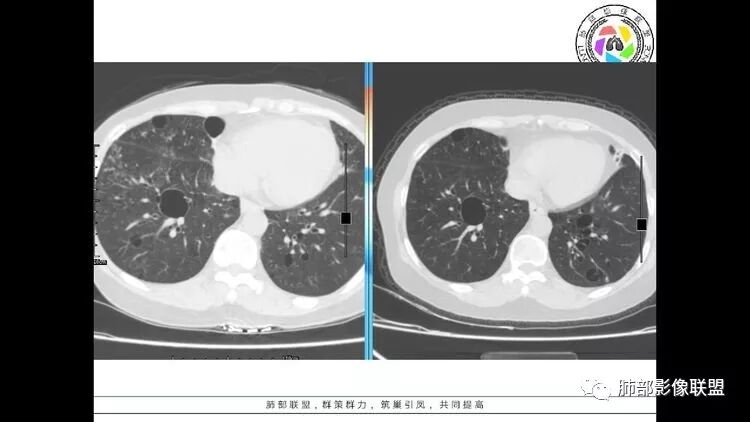

老年女性,眼炎入院,血常规正常,双肺多发囊状影,病变随机分布,形态单一,与血管关系密切,考虑LIP。左下肺混合GGO,边界尚清,贴近囊腔,鉴别腺癌。炎症指标无异常暂不考虑感染性病变。

胸CT:1.双肺多发囊性变,以中下肺为主,病变边缘可见肺动脉,部分囊内可见分隔及肺动脉,双下部分肺野周围可见小叶中心结节及树丫征。

2 左肺上叶尖后段 右肺上叶前段 右肺下叶外基底段 结节影,边界清楚,可见柔软毛刺,左肺下叶后基底段混合密度影。

3.纵隔淋巴结肿大?,以主动脉弓为界向上向下增大。

考虑:淋巴瘤肺浸润,眼部症状考虑与此有关;LIP?;继续鉴别肺腺癌?血管炎?。